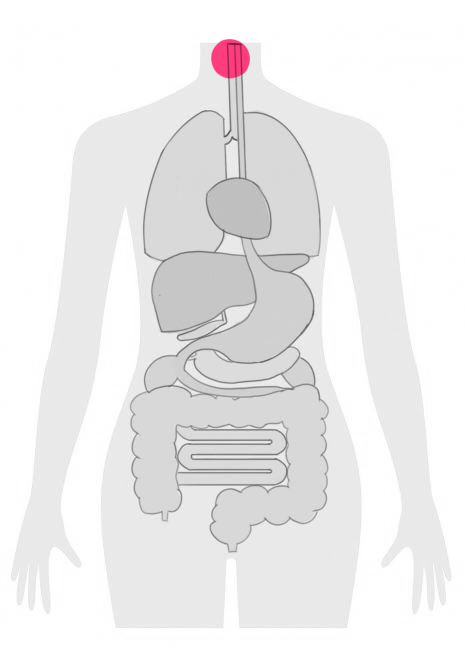

甲状腺がんは、甲状腺という首の前部に位置する腺から発生するがんです。

甲状腺がんの場合、抗がん剤治療は主に進行したがんや再発したがんの治療に用いられます。

しかし、がんが進行して他の臓器に転移してしまった場合や、手術や放射線治療だけでは効果が不十分な場合には、抗がん剤治療が考慮されます。

特に、無分化がんや髄様がんのような進行が早いタイプの甲状腺がんでは、抗がん剤治療の導入が早期に検討されることがあります。